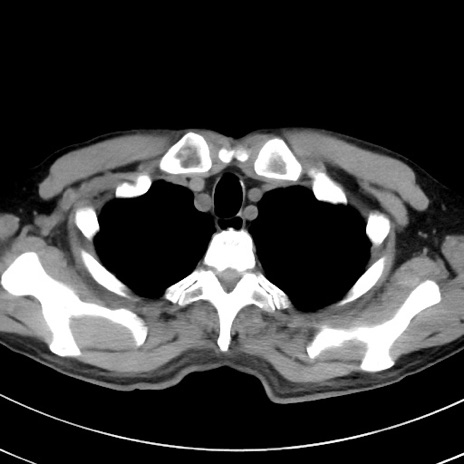

症例38(横断像)

【症例】70歳代 男性

【主訴】腹痛・嘔吐

【現病歴】昨晩より、嘔吐・腹痛あり。今朝になっても嘔吐あり。来院。

【既往歴】心臓バイパス手術、開腹胆摘、腸閉塞

【身体所見】BP 107/71mmHg、HR 116/min、腹部:平坦、軟、下腹部に軽度圧痛あり。反跳痛なし。

【データ】WBC 15100、CRP 0.32